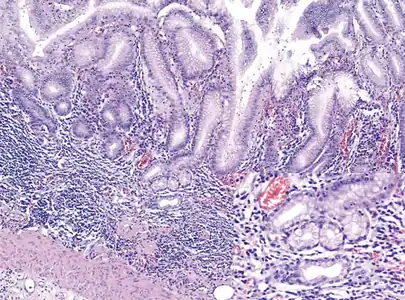

Histopathology of antral mucosa with atrophy. H&E 10x. Antral gastric mucosa with accentuated atrophy because replacement by extensive intestinal metaplasia. Histopathology of fundic mucosa with atrophy. H&E 10x; square 20x. Fundic-corporal gastric mucosa with extensive loss of gastric glands, partially replaced by pseudo-pyloric metaplasia.

Histopathology of fundic mucosa with atrophy. H&E 10x; square 20x. Fundic-corporal gastric mucosa with extensive loss of gastric glands, partially replaced by pseudo-pyloric metaplasia.